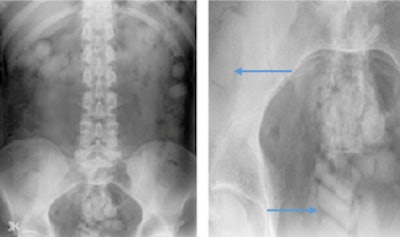

X-ray of 24-year-old woman shows a solitary well-defined radiopaque density lying within the pelvis, outside of the bowel lumen.The authors have also encountered cases of colonic packing. They have seen smooth, well-defined radiopaque densities -- sometimes variable in size and shape -- scattered throughout the bowel lumen. The characteristic 'double condom' sign may be visible, and the complications can include bowel obstruction or perforation.

X-rays show smooth, well-defined radiopaque densities scattered throughout the bowel lumen. Blue arrows demonstrate the characteristic 'double condom' sign.CT and x-ray facilitate evaluation for associated complications of gastrointestinal obstruction or perforation and are less limited by visceral gas. Ultrasound may be useful in younger patients, particularly in pregnant women. Appearances vary depending on the method of concealment, but are morphologically similar to those on CT.